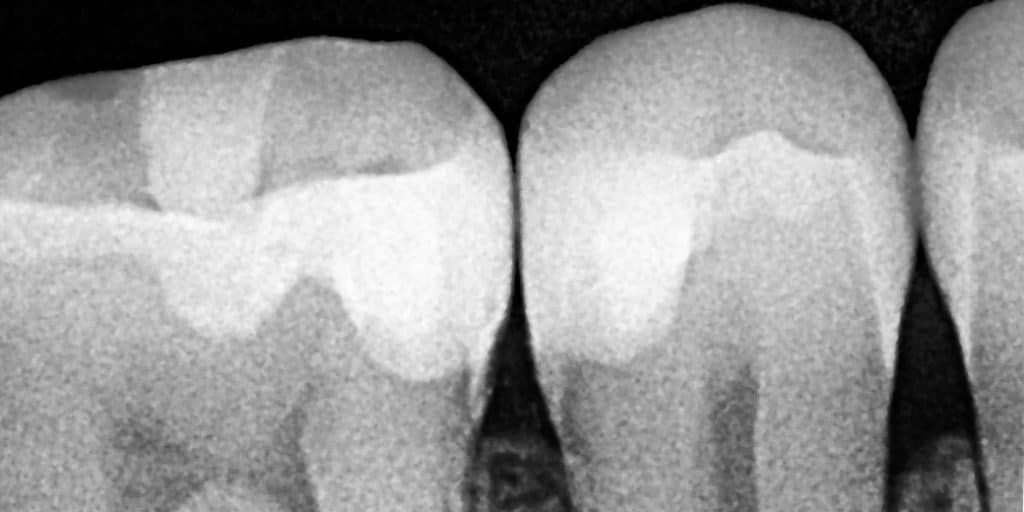

X Ray ... before